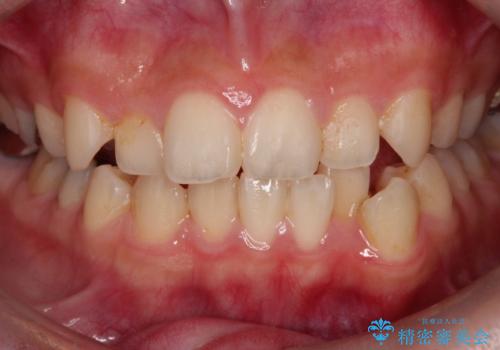

上下のガタガタのマウスピースによる非抜歯矯正